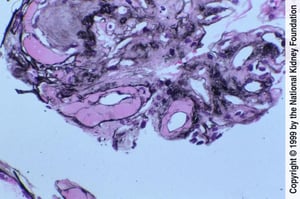

Sono caratteristiche le lesioni della glomerulosclerosi intercapillare diffusa o nodulare; aree di nefrosclerosi nodulare possono essere attribuite a lesioni di Kimmelstiel-Wilson. Vi è una marcata ialinosi, così come un'arteriosclerosi delle arteriole afferenti ed efferenti; possono essere presenti fibrosi interstiziale e atrofia tubulare. L'espansione della matrice mesangiale sembra essere correlata all'evoluzione verso l'insufficienza renale terminale (1).

La formazione di noduli acellulari all'interno della matrice mesangiale è una caratteristica distintiva della nefropatia diabetica (colorazione con acido periodico di Schiff, ×200).

Imagine fornita da Agnes Fogo, MD, and the American Journal of Kidney Diseases' Atlas of Renal Pathology (vedi www.ajkd.org).